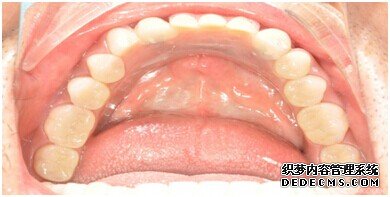

整个种植牙完成后的效果图

种植牙整个过程完成后,刘女士非常满意自己的牙齿,并且表示以后一定会遵照医生的嘱咐好好注意自己的口腔健康,每晚一定会好好刷牙,饭后漱口,当然也会注意保护这颗种植牙!